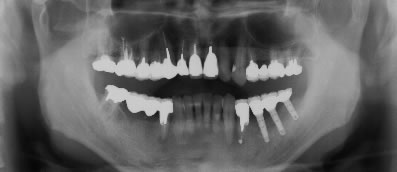

写真1〜4はそれぞれ術前・後の左側口腔内写真とレントゲン画像です。

写真1(施術前)

写真2(施術前のレントゲン画像)

写真3(施術後)

写真4(施術後のレントゲン画像)